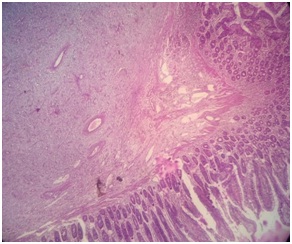

Photomicrograph showing the submucosal origin of the polyp (H&E, 4x).

A 49-year-old male patient presented in the emergency department with acute pain abdomen. Upon auscultation of the abdomen, bowel sounds were found to be consistent with mechanical bowel obstruction. Digital rectal examination did not show the presence of feces, mucus or blood. Laboratory investigations showed total leukocyte count 9,400/mm3 with 75% polymorphs, Hb 12.2 g/dl, creatinine 0.9 mg/dl, urea 41.3 mg/dl, sodium 135 mmol/l and potassium 4.5 mmol/l. An upright plain abdominal film revealed small bowel obstruction, with marked small bowel air-fluid levels. Abdominal ultrasound revealed a well-defined hypoechoic lesion measuring 2.8x2.3 cm noted within the bowel loop with evidence of intrusion of proximal bowel loops within the bowel in right hypochondriac –lumbar region. CT scan showed luminal soft tissue density mass in right upper quadrant small bowel loop, possibility of gastrointestinal stromal tumour (GIST) was suggested [Table/Fig-1]. During exploratory laparotomy an ileal intussusception due to a mass lesion 50 cm proximal to the ileocecal junction was found [Table/Fig-2]. Partial ileal resection and anastomosis were performed. On gross examination, cut opened part of ileum measured 13.5 cm in length. Inner surface showed normal mucosal folds along with a solitary sessile polypoidal lesion at the site of intussusception measuring 3.8x 2.5x1.5 cm [Table/Fig-3]. On light microscopic examination, the polypoidal lesion at the site of intussusception showed a mesenchymal sub mucosal lesion extending upto serosa comprising of plump spindle cells in a background of loose fibro-myxoid stroma, proliferative blood vessels some of which appeared to be hyalinized along with mixed inflammatory infiltrate predominantly eosinophils [Table/Fig-4,5 and 6]. Immunohistochemistry for CD-117 was negative [Table/Fig-7].